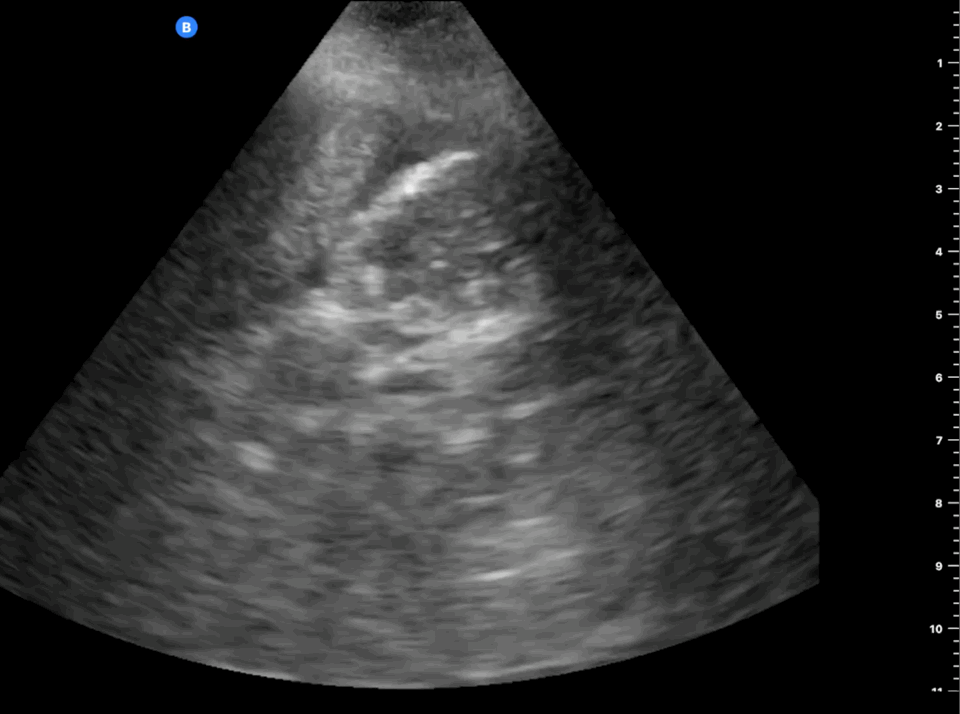

Free fluid Above the Liver, Beneath the Diaphragm